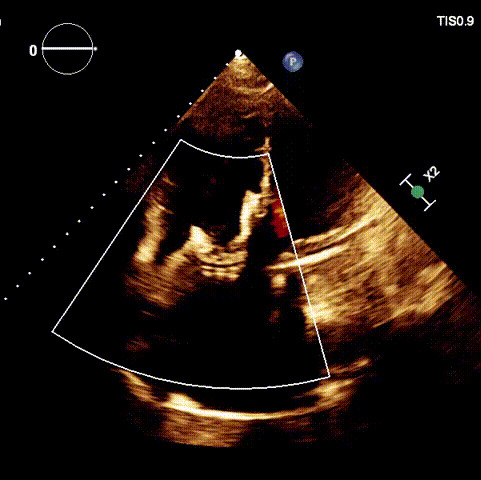

術前超聲心動圖及經食道超聲提示

1.二尖瓣位機械瓣位置及功能未見異常;2.雙房及右室明顯擴大(左房收縮容積115ml,右房收縮容積370ml,右室中段左右徑65mm,右室FAC37%),下腔靜脈及冠狀靜脈竇擴張(下腔靜脈直徑44mm,冠狀靜脈竇直徑22mm);3.極重度三尖瓣反流(FTR 6+)。

術前超聲